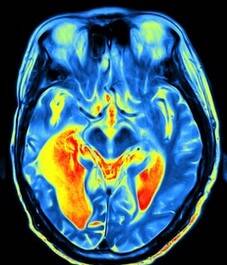

Een doorbloedingsscan, Pet-scan (Positron Emission Tomography)

of SPECT scan (Single Photon Emission Computed Tomography) toont het functioneren aan, of er bijvoorbeeld een doorbloedingsstoornis of verhoogde activiteit is. Het spoort dus veranderingen in bloedstroom en metabolisme in hersenen. Hiermee is diffuus letsel vaker wel zichtbaar te maken maar ook niet altijd.

• De Pet scan maakt gebruik van kleine hoeveelheden radioactieve materialen, radiotracers genaamd, een speciale camera en een computer om de orgaan- en weefselfuncties te beoordelen. Door lichaamsveranderingen op cellulair (neuraal) niveau te identificeren, kan de PET-scan afwijkingen of een ziekte detecteren voordat het duidelijk wordt in andere beeldvormingstests. Het meet niet alleen doorbloeding, maar ook de suikerhuishouding (glucosemetabolisme) en zuurstofopname. De ingespoten radioactieve stof verdwijnt snel uit het lichaam en is niet schadelijk. Diffuus letsel is soms beter in beeld te brengen dan bij een MRI-scan. Als er twijfels zijn over een diagnose, zou deze scan soms het antwoord kunnen geven. Echter het inzetten van deze techniek vereist een urgente medische situatie. Niet om bewijslast te leveren over langer geleden opgelopen letsels.